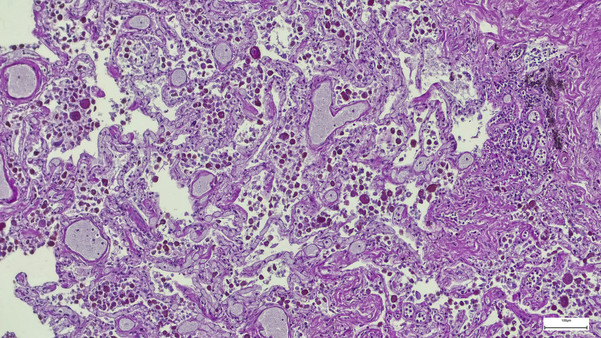

Los modelos de tumores subcutáneos (SC) han desempeñado un papel importante en el descubrimiento de fármacos contra el cáncer durante muchos años. El uso de estos modelos es un paso crítico a lo largo de la cascada de descubrimiento de fármacos. Los estudios in vivo que utilizan modelos tumorales SC se incorporan a los ensayos farmacodinámicos para garantizar la inhibición de la diana y la inhibición adecuada de la diana a lo largo del tiempo.

En Labcorp, ofrecemos más de 500 modelos de xenoinjertos singénicos, de tumores humanos y derivados de pacientes, incluidos modelos resistentes a los medicamentos y especializados, y estamos validando continuamente nuevos modelos. Se utilizan métodos basados en calibradores para evaluar el crecimiento tumoral de nuestros modelos tumorales SC y se pueden incorporar métodos de imagen adicionales para probar criterios de valoración funcionales y mecanicistas.